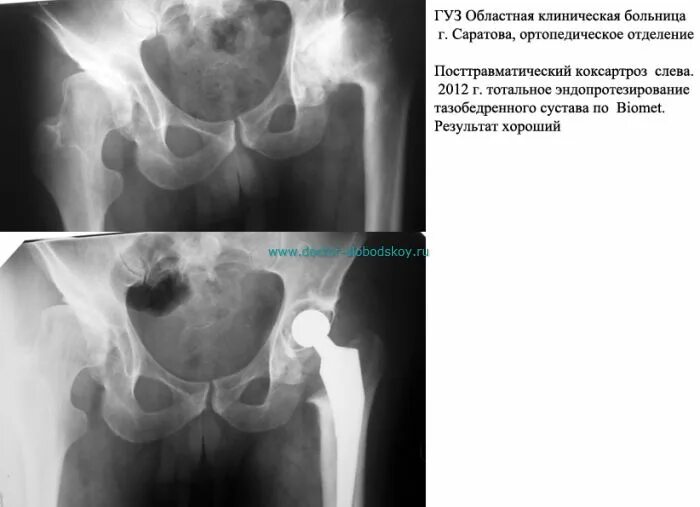

Коксартроз коленного сустава тазобедренного